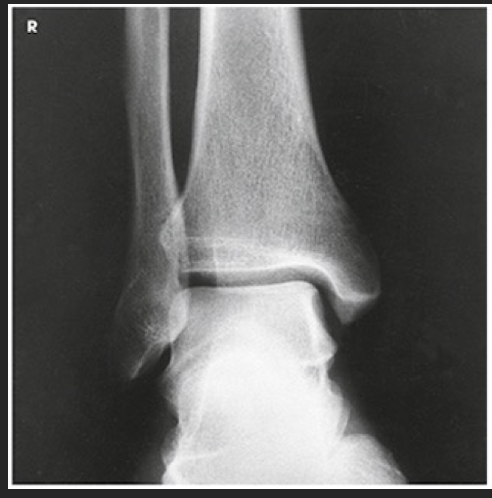

Name this projection.

AP ankle

Describe how the anatomy of interest is positioned.

Patient is seated, or supine, with the affected leg extended onto the IR; the ankle is in true anatomic position w/ dorsiflex

Where does the CR enter?

Perpendicular through the ankle joint (midway between malleoli)

Is there any rotation?

No

What structures are seen?

Ankle joint, distal tib/fib (medial and lateral malleoli), and the proximal talus

Which aspect of the ankle is best visualized?

Medial

What anatomy will overlap?

Tibiofibular joint and slight superimposing of the talus and distal fibula